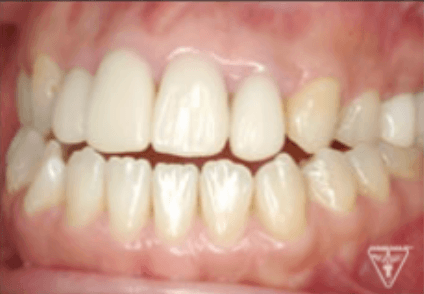

治療後